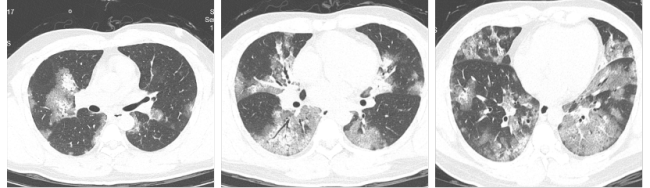

刘先生是一名身体健康的上班族,在这次流感季节中不幸成为重症患者。起初他只是有些轻微咳嗽咳痰,以为是普通感冒并未在意。然而几天后,他的症状加重,出现气急情况。到医院就诊后,检查结果显示他感染了甲型流感,且胸部CT显示两肺有严重的磨玻璃样渗出,即“白肺”。医生立即将其收治入院,并进行吸氧、抗病毒和激素治疗。经过医护人员的努力,刘先生病情逐渐稳定,最终康复。